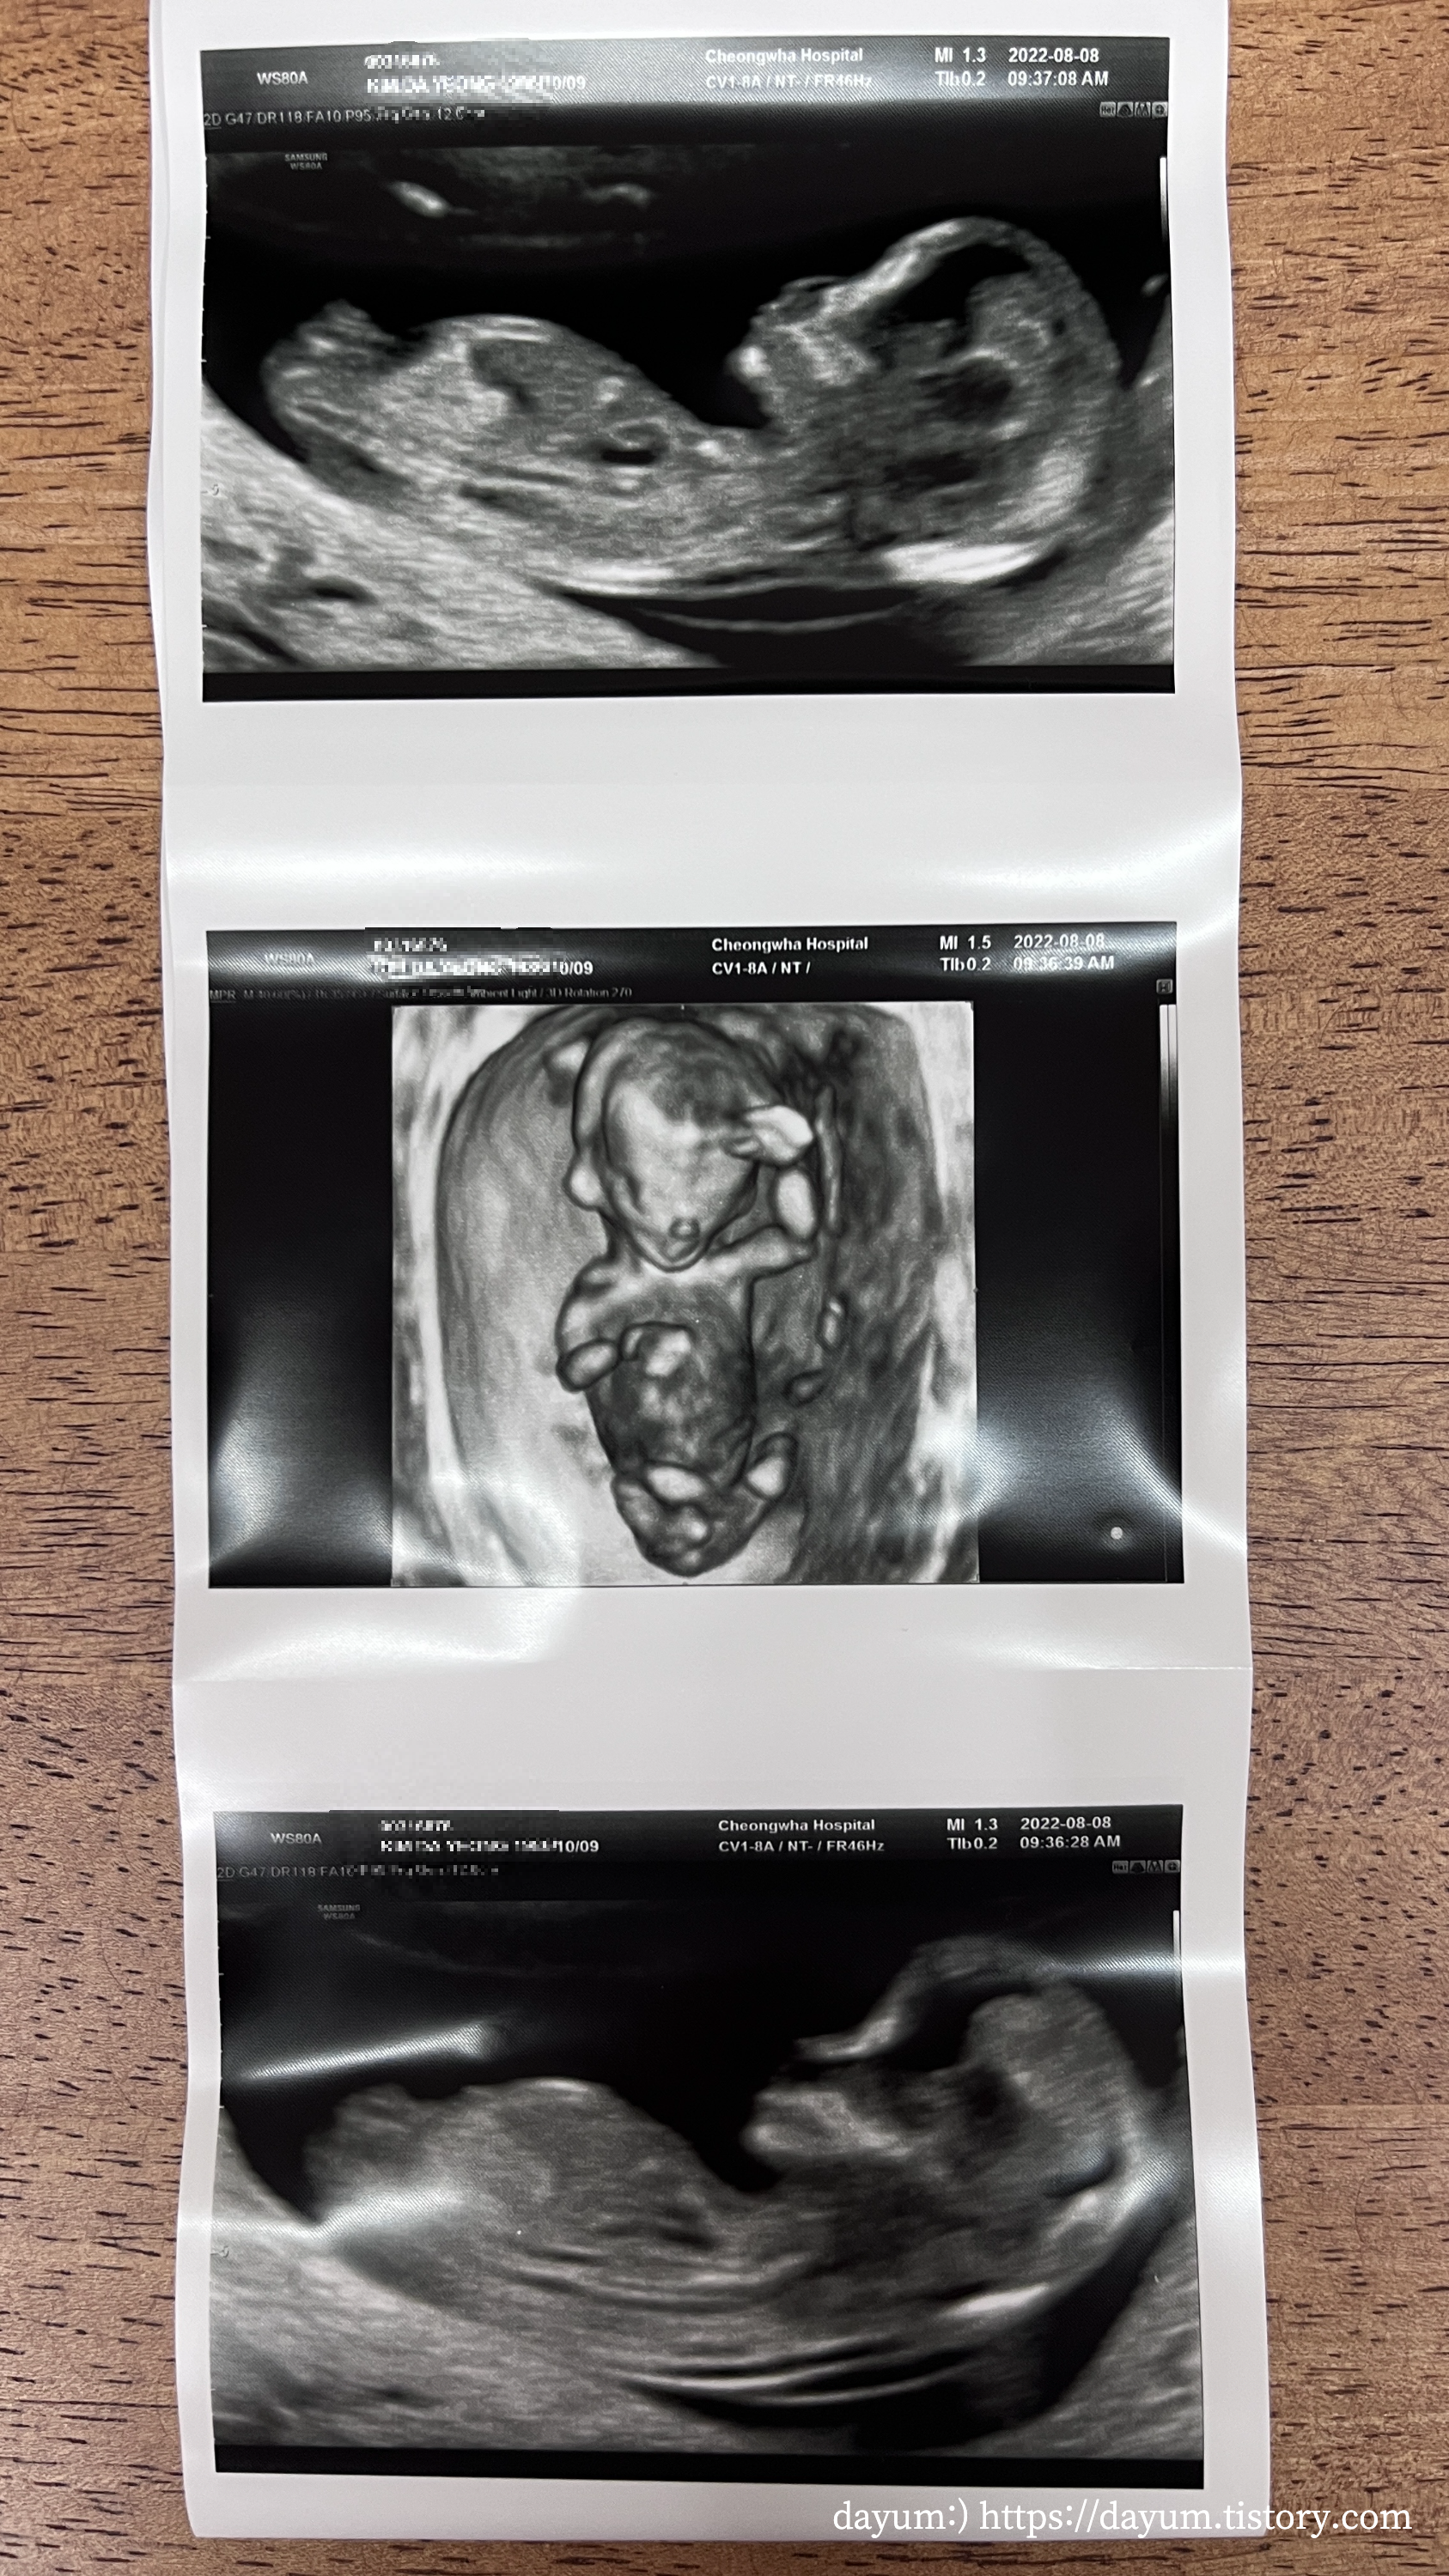

입체초음파는 태아가 협조를 잘 해줘야 금방 끝난다고 했는데 조이는 잘 자고 있다가 끝날 때 쯤 일어나서 약 7분만에 끝났다.

생각보다 배꼽 아래에 있었는데, 두다리를 꼬고 있고, 한쪽 팔로 가드를 치고 있었다.

태아의 뇌는 나비모양으로 잘 형성되었고, 코뼈, 상악, 하악 모두 잘 만들어졌다고 한다.

탯줄로 혈액이 공급되는 것도 봤고 목투명대는 1.31mm로 정상범위에 있다고 한다.

귀염둥이 ㅠㅠ 언제 이렇게 자랐어